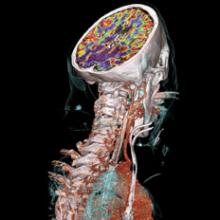

With a patient on the table, an interventional radiologist follows the movement of his catheter through a maze of arterial vessels. As he weaves his catheter through an intricate web of arteries to reach the coronary arteries and the area of interest, he gets constant real-time feedback from the monitors so he can carefully position the catheter to perform the intervention.